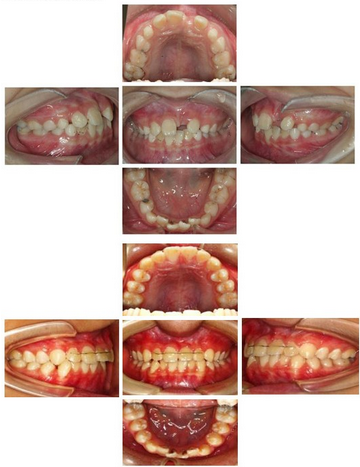

功能矫治前中后合像对照: